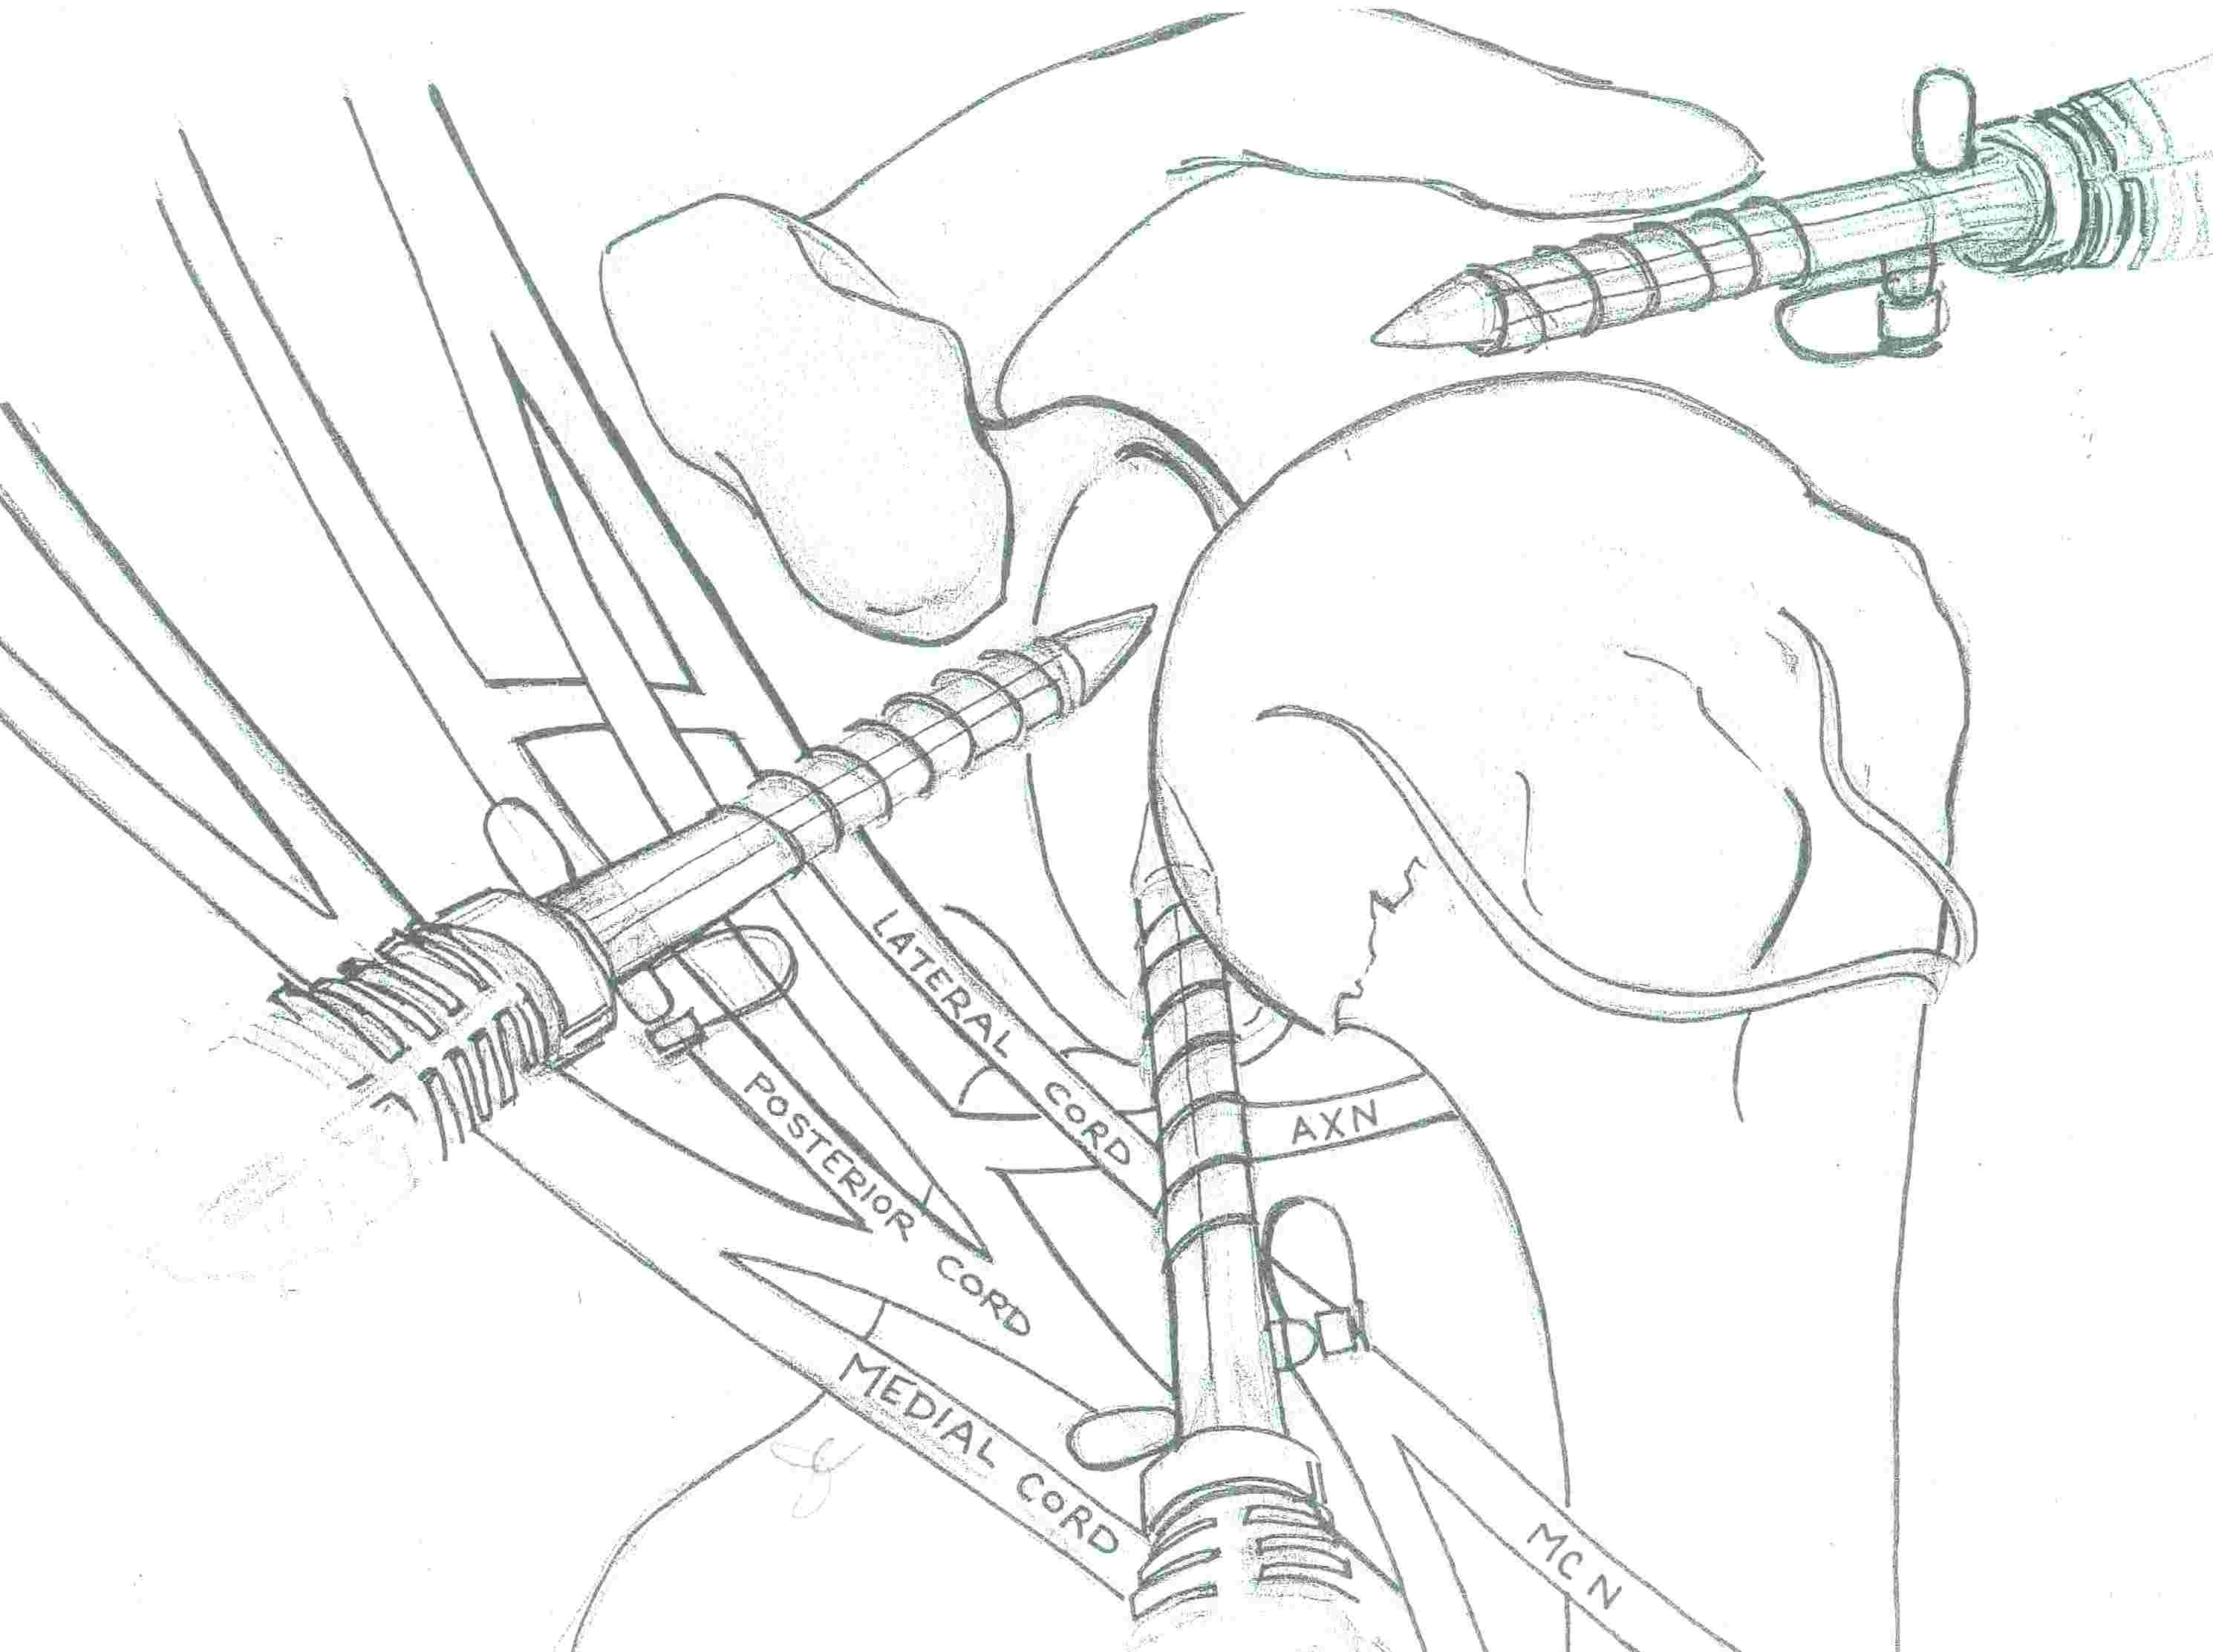

Portals

| Posterior portal | Anterosuperior portal | Anteroinferior portal |

|---|---|---|

| 2 cm below and 2 cm medial to posterolateral acromion |

Below AC joint Rotator interval at angle between biceps and glenoid |

Inferior and lateral to Anterosuperior portal Midpoint of subscapularis |